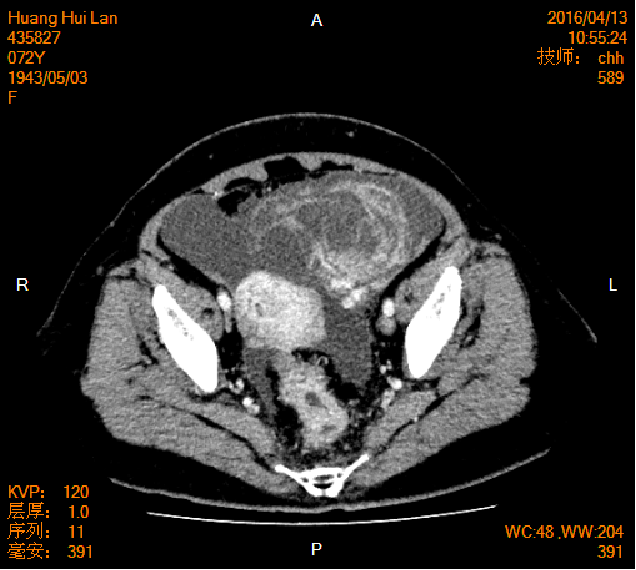

2016-04-13胸腹盆CT

左侧附件区肿块,代谢活跃,考虑卵巢囊腺癌;直肠壁增厚,代谢活跃,考虑直肠癌并周围淋巴结转移可能性大,建议肠镜检查;双肺多发结节,考虑转移瘤;腹腔积液